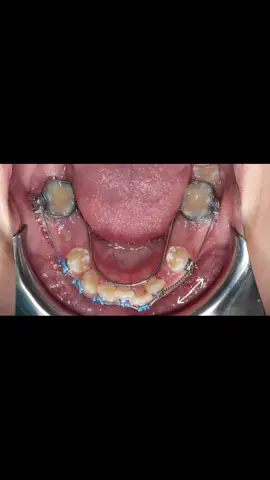

Preservation and management of space in the late mixed dentition 🔑#orthodontist #orthodontics #braces #ortodontia #ortodontista